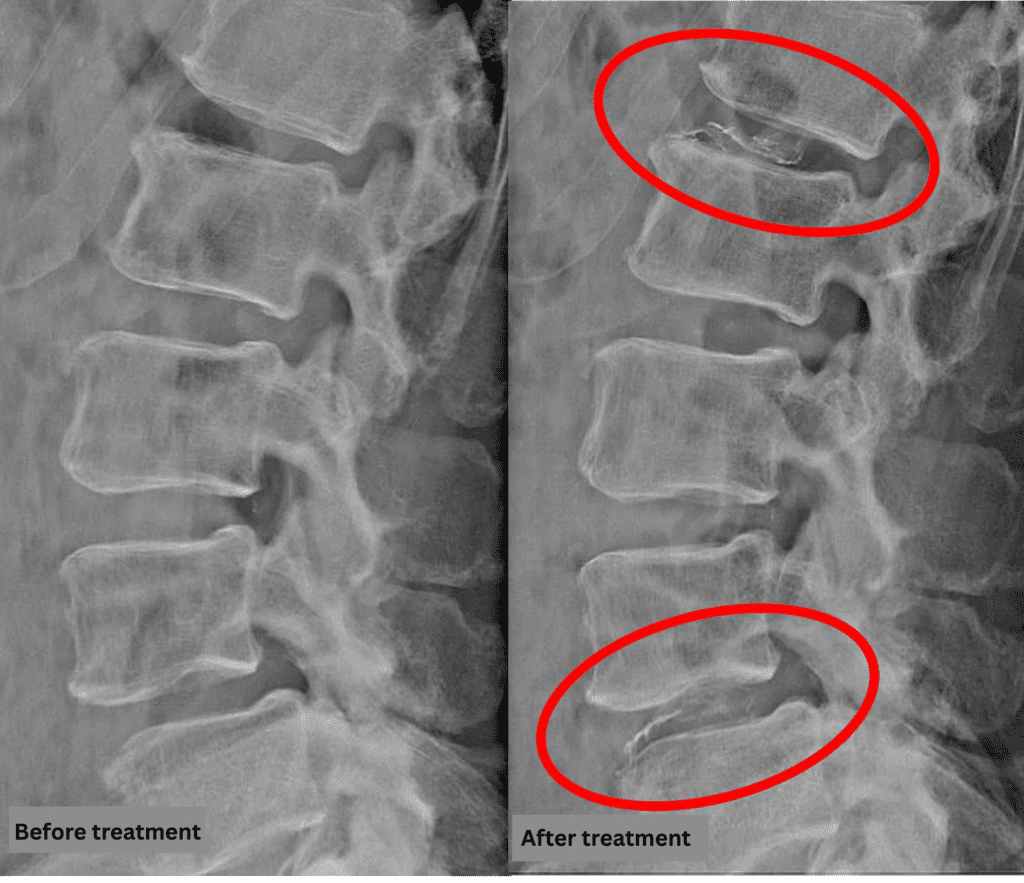

After consulting with the patient, the Cellgel Method was performed on L1/2 and 4/5.

The treatment was performed by Dr. Ohara.

The treatment took about 20 minutes.

After resting in the recovery room, the patient was able to walk home unaided.